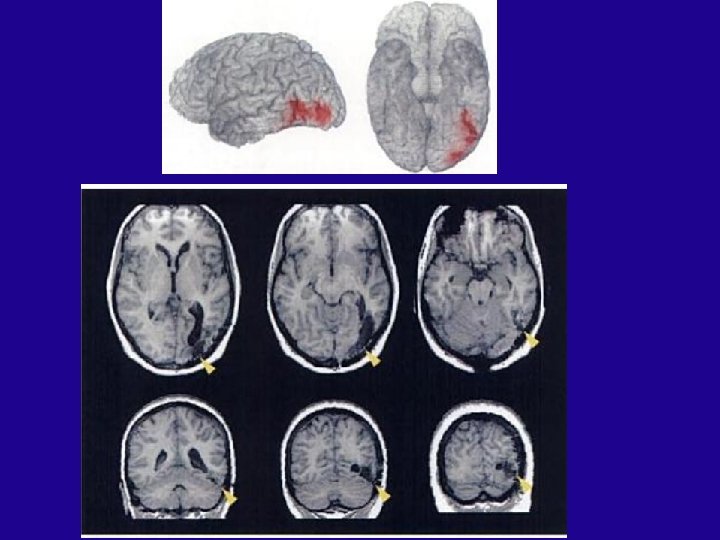

Broca Aphasia (Expressive aphasia) Left hemisphere 44 & 45

Brain of “Tan” Leborgne (for the last 20 years of his life, the only word M. Leborgne could say was “tan”)